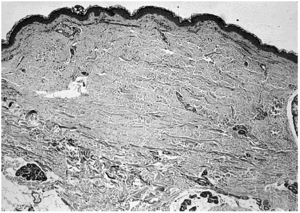

El estudio histopatológico evidenció únicamente una discreta atrofia epidérmica y un engrosamiento de las fibras colágenas en la dermis reticular en una de las biopsias (paciente 1) (fig. 3). En ninguna muestra histológica se evidenció elastosis actínica.

Fig. 3.--Mínima atrofia epidérmica. Engrosamiento de las fibras de colágena en la dermis reticular (H-E, ×40).